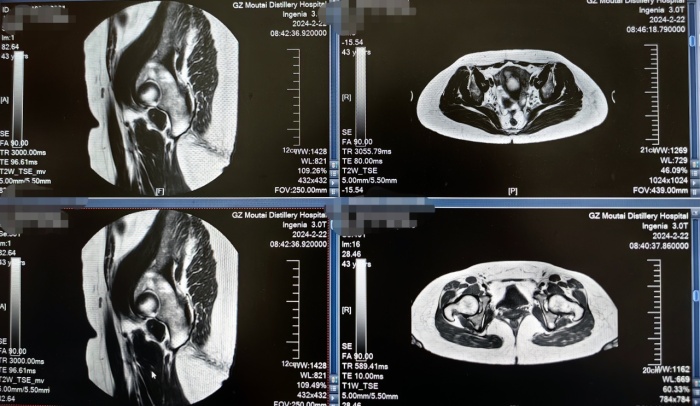

患者陈女士,29岁,两次剖宫产后再次妊娠,彩超提示剖宫产瘢痕妊娠,即孕囊着床在子宫的剖宫产瘢痕处,辗转几家医院检查后,均被告知清宫风险很大。得知贵州茅台医院可开展“海扶”无创治疗技术,故就诊于贵州茅台医院。经复查彩超提示,孕囊大小为15mmx23mmx16mm,可见胎心,孕囊着床在子宫切口瘢痕处,血HCG高达45200mIU/ml,胚胎活性很强。由于子宫切口部位的肌层非常薄弱,盲目清宫极易造成子宫穿孔、致命性大出血导致子宫切除,甚至危及生命。

经过对患者进行严格的术前评估和详细的病例讨论,海扶技术团队一致决定先进行海扶预处理后,再对其行清宫术清除瘢痕部位妊娠组织,以减少术中出血。2月27日,贵州茅台医院为患者进行了海扶治疗,术前超声造影提示病灶内部见丰富血流;术中患者全程清醒,无任何痛苦,生命体征平稳;术后超声造影提示病灶内部无明显血供,提示病灶消融满意。整个手术历时仅16分钟,完美阻断胚胎血供。术后6小时,患者可自行下床,活动自如。术后第二天,我院及时为其行清宫术,清除瘢痕部位妊娠组织,术中出血少,手术顺利完成。术后3天,患者顺利出院。此次手术不仅预防了术中难以控制的大出血,还顺利保住了子宫。